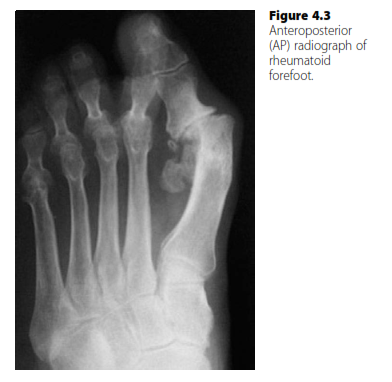

Foot and ankle structured oral questions3: The rheumatoid foot EXAMINER : Please have a look at this radiogra…